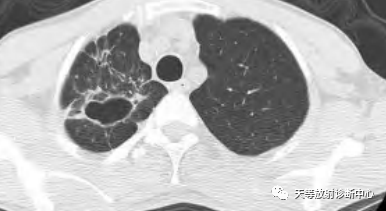

影像学表现:整体观察肺内多发病灶,散在分布,病灶的主要形态为:多发大小不等肺气囊、多发结节共同存在。

1、肺气囊大小不等,张力较大,圆形膨胀感强,周围可见大小不等结节影;

2、病灶主要沿支气管血管束方向分布,部分病灶达到胸膜下;

3、支气管间质增厚;

4、结节影大小不等,小的呈树芽征堆积,大的部分到达胸膜小,具有糊墙征,性格较温和。仔细观察病灶呈四边形、多边形,边缘刀切感,边界模糊。